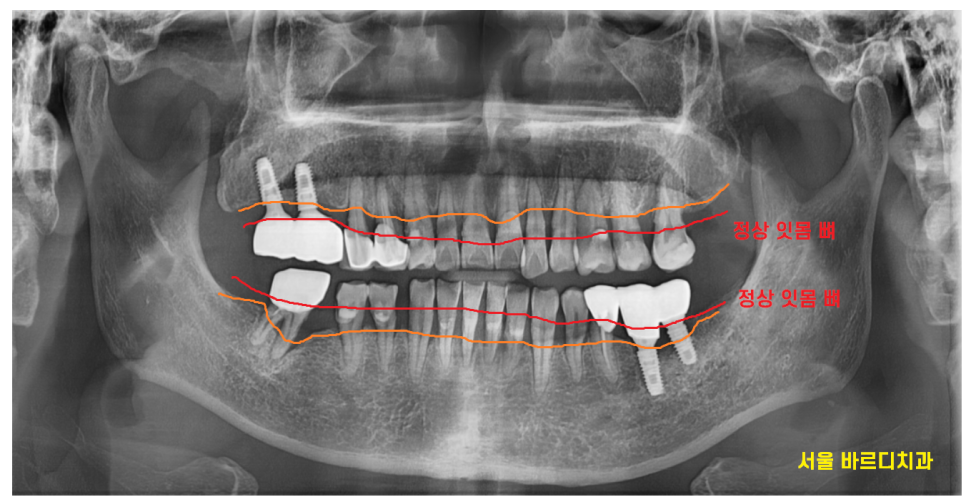

X-RAY를 촬영해보았을 때

전형적인 풍치 증상이네요~

잇몸뼈가 빨간색 라인까지

치아 머리 부분까지

채워져있어야하지만

환자분은 주황색 부분까지 내려간 상황이었습니다.